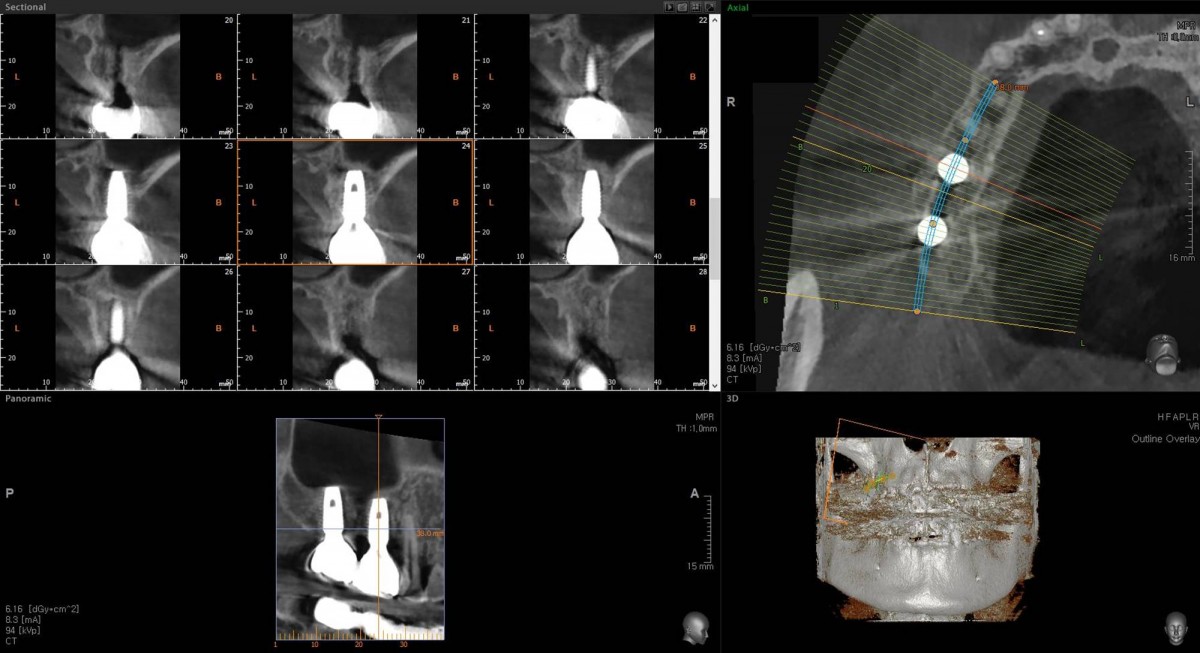

Socket Lift and Implant Placement in the right maxilla.

<GCacg> A 56-year-old male patient complained of pain in the right upper and lower jaws. And he wanted the upper first molar to be pulled out first.